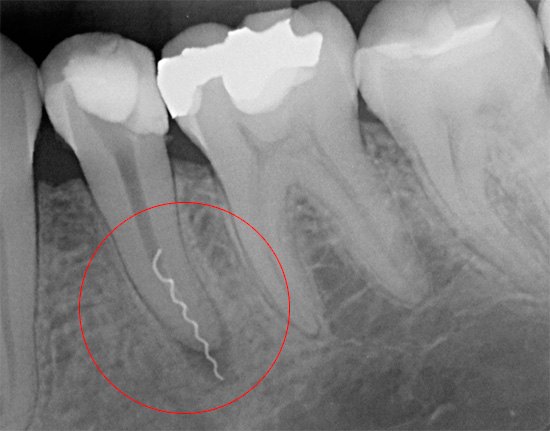

Lascando uma ferramenta em um canal

Se o dentista encontrar pela primeira vez uma complicação como uma quebra do instrumento no canal, na maioria dos casos o médico entrará em pânico (o momento psicológico é acionado - afinal, isso é um erro médico). No entanto, isso, embora não seja o mais frequente, mas, no entanto, um erro de trabalho bastante comum, pode ser corrigido, levando em consideração tecnologias e métodos modernos, e o dente pode ser salvo.

Se durante a limpeza do canal uma parte do instrumento endodôntico se romper nele, se for deixado no canal, o dente começará a doer imediatamente ou após algum tempo. Isso se deve ao fato de que um pedaço do instrumento preso no canal não dá ao médico acesso ao ápice da raiz, devido ao qual permanece uma parte do nervo ou uma infecção não tratada que começará necessariamente a se multiplicar e pode levar a problemas muito grandes no futuro.

Para evitar possíveis complicações futuras, a remoção imediata dos detritos é realizada usando vários métodos. Por exemplo, o método ultrassônico de "nocautear" um fragmento é atualmente usado ativamente. Outro método de extração é passar um canal ao lado de uma ferramenta presa, expandir, enxaguar, agarrar e removê-lo.